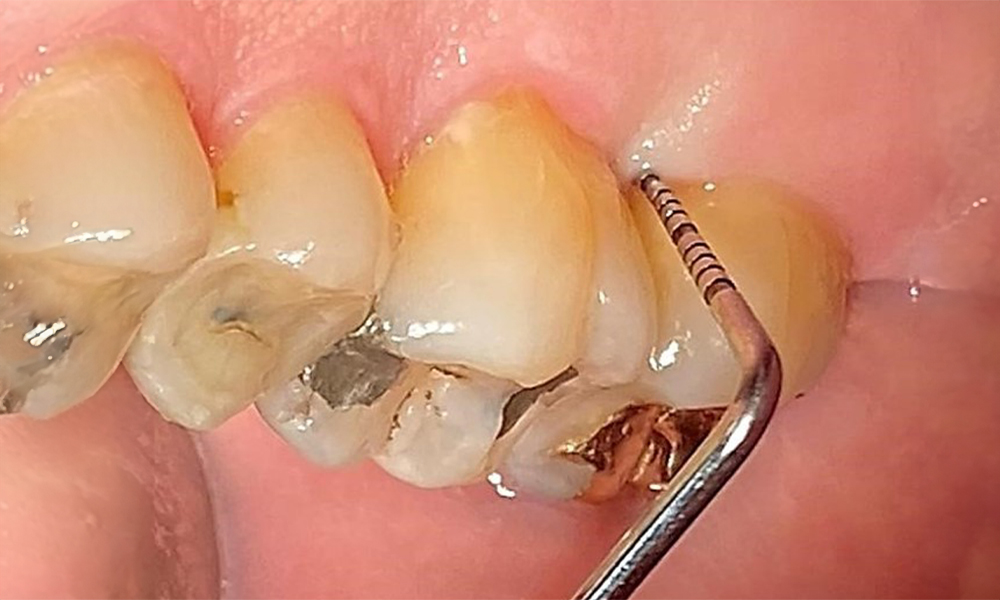

Sondierung für die Befundaufnahme in Rg. 27 mesiopalatinal. © Dr. R. Krapf

Abb. 8: Sondierung für die Befundaufnahme in Rg. 27 mesiopalatinal. © Dr. R. Krapf

Der Patient ist ein gut eingestellter Diabetiker. Somit ergibt sich aus der Anamnese kein erhöhtes Komplikationsrisiko für die Behandlung. Grundsätzlich ist vor jeder Behandlung der HbA1c-Wert abzufragen. Die Befundaufnahme intraoral ist entscheidend für den Bedarf an dentaler und parodontaler Therapie. Aufgrund der Parodontitis ist ein parodontaler Befund mit Taschentiefensondierung und Blutungsstatus in jeder Sitzung unerlässlich (Abb. 8). Dieser gibt den individuellen Therapiebedarf vor und es kann auf eine mögliche Progression der parodontalen Vorerkrankung reagiert werden.